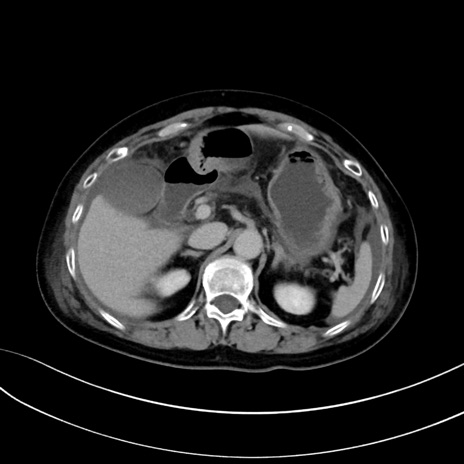

症例13 CT(横断像)1日半後